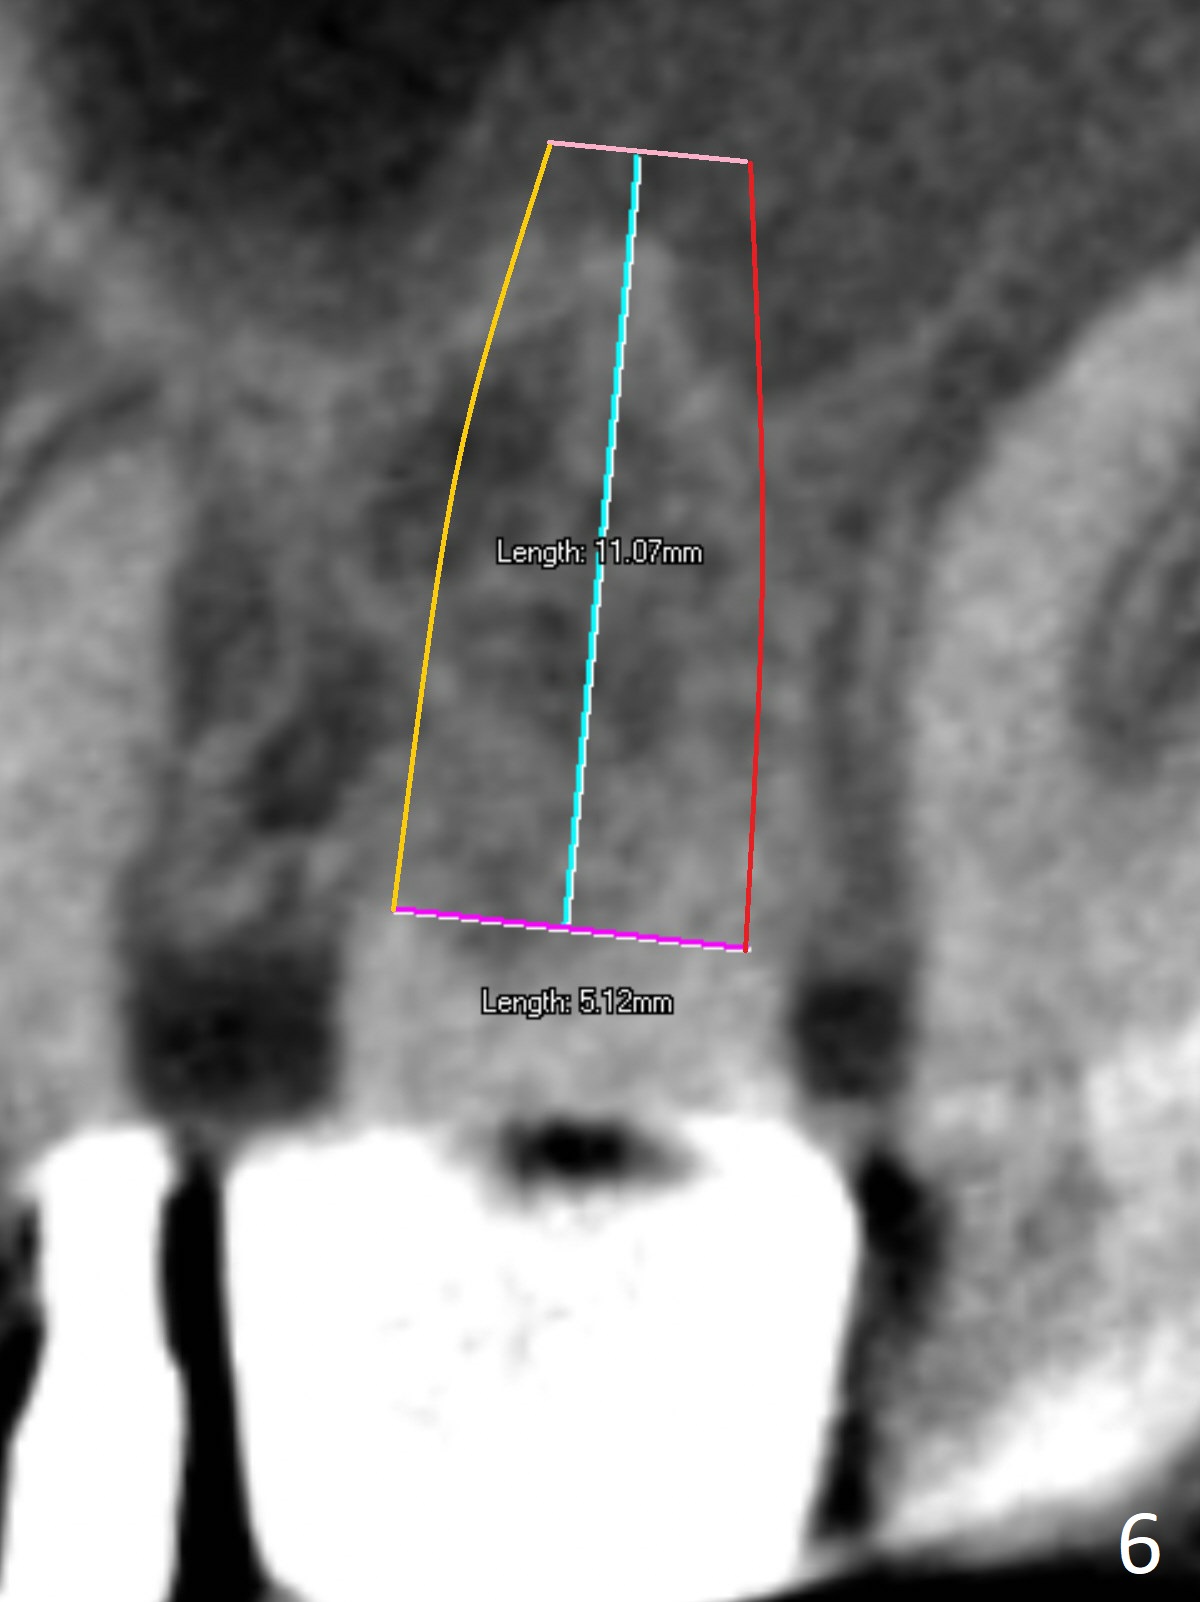

A 70-year-old woman fractures the crown at #14 (Fig.1).  A 5x11 mm implant will be placed at the septum (Fig.2).  Osteotomy depth can be determined using bony (Fig.3 with stopper) or gingival (Fig.4,5 with vision) landmark.  The CT was taken 5 years earlier.  Sagittal (Fig.6) and axial (Fig.7) sections confirm suitability of the 5x11 mm implant for the site.  Prepare surgical handpiece for sectioning the tooth for extraction.  After drills, use Magic Expanders for sinus lift.  Place Vanilla Graft prior to dummy implant(s).  A bone-level implant crown may be easier to be repaired if the proximal contact is not ideal.